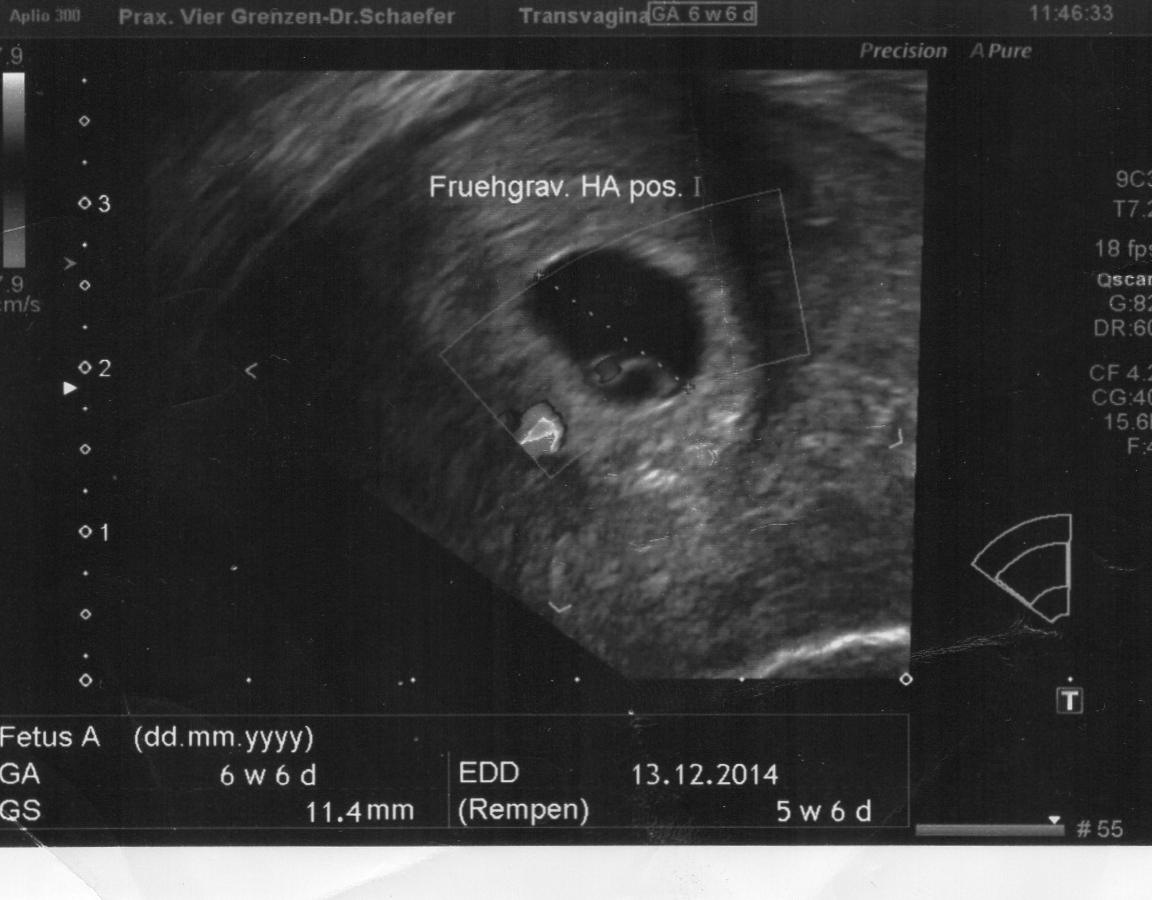

Heute gab es ein Fotoshooting der besonderen Art beim Opa auf Arbeit. Sein Kollege, der stellvertretende Chefarzt der Kinderklinik und gleichzeitig Guru des Ultraschalls, hatte sich bereit erklärt den werdenden Eltern noch ein paar aktuelle Fotos zu machen. Leider gab es kein 3D, aber dafür ein paar süße Fotos und vor allem Videos unseres Sohnemannes, der sich die ganze Zeit über ruhig verhielt und sich der Kamera, äh dem Schallkopf stellte.